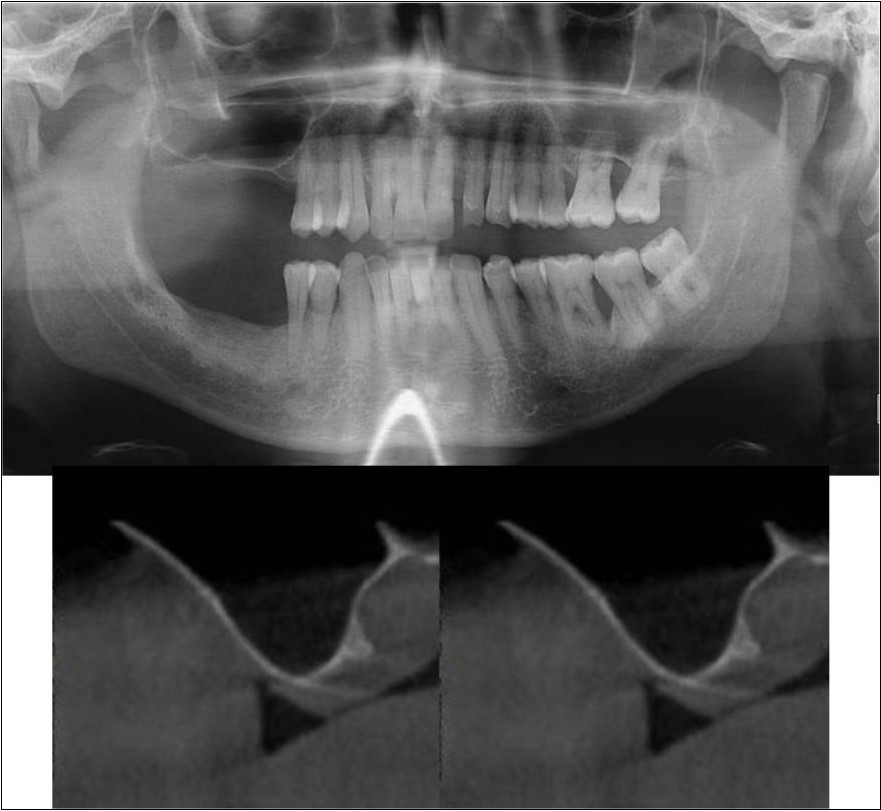

Case Report 1:

A 40 years old male patient reported to the Department of Oral and Maxillofacial Surgery, D.A.P.M.R.V Dental College and Hospital with a chief complaint of inability to chew food because of loose teeth from past one year. The teeth were extracted an year ago in the right upper and lower back tooth regions because of gross loss of tooth structure and poor prognosis for root canal treatment. Patient was a controlled diabetic and was on medication for the same. Patient did not give history of any existing sinus pathologies. All possible rehabilitative options were explained to the patient and a treatment plan of replacement of missing teeth with implant supported prosthesis using two dental implants was finalized.

Clinical and Radiological Assessment:

1.Partially edentulous maxillary and mandibular arches with missing 16, 17, 18, 46, 47, 48;

2.Increased pneumatisation of right maxillary sinus;

3.Chronic generalized periodontitis;

4.Inter-ridge space adequate to place implant (25mm).

Treatment: Direct sinus augmentation using calcium phosphosilicate (CPS) in relation to 16,17 followed by implant placement as a single step procedure was advised. Lateral window was created and calcium phosphosilicate putty (2cc) was dispensed as the graft material through the lateral osteotomy site to maintain the elevated sinus membrane followed by placement of two dental implants through the crestal approach measuring 3.75 x 11.5mm under local anaesthesia and strict aseptic protocols. At the end of 6 months, a repeat CBCT scan was advised to evaluate the increase in bone height. (Figure 7a-c, pre-treatment; Figure 8a-c, post-treatment)

Figure 7.(a-c) Pre-treatment OPG and cross sections of CBCT showing residual alveolar bone height for Case No.1;